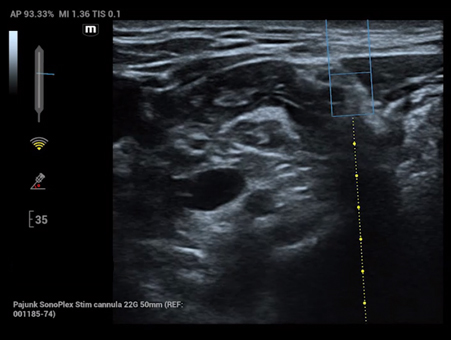

Reimagined safety and adaptability

MindrayŌĆÖs Anesthesia Ultrasound solutions address your biggest perioperative challenges such as treatment efficacy and patient safety, to improve patient outcomes in the operating room. We recognize the human side of healthcare and your role in providing best-in-class patient care, which is why we designed products suited to your clinical needs in this environment.